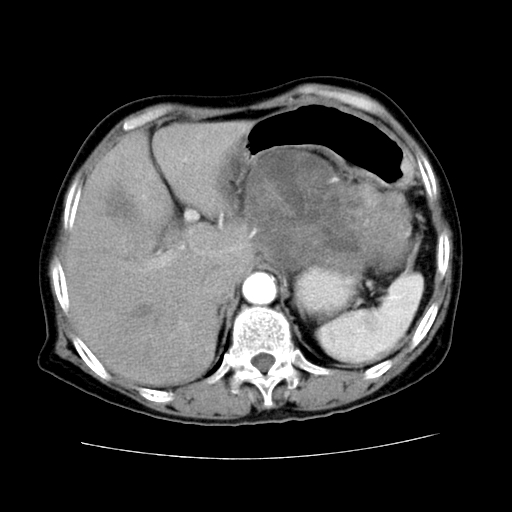

女性,72岁。

主诉中上腹部疼痛不适1年余。

胰腺尾部不规则巨大略低密度肿块,界限清楚,内密度不均,增强动脉期不均匀强化,门脉期明显退减并低于胰腺密度,肿瘤包埋于脾血管。多考虑;来源于胰腺尾部的“胰腺癌”。

胰腺尾部不规则巨大略低密度肿块,界限清楚,内密度不均,增强动脉期不均匀强化,门脉期明显退减并低于胰腺密度,肿瘤包埋于脾血管。多考虑;来源于胰腺尾部的“胰腺囊腺癌。

考虑胰体尾部囊腺癌可能性大。肝右叶可疑转移.

1、这个病例确实有点难。影像主要显示胰腺体尾部占位,我们当初也是诊断胰体尾部囊腺癌可能性大,而且读片会上也很多人这么诊断的。

2、手术所见:打开腹腔发现胃与胰腺体尾部可见肿块,大小约10×8×11cm,质硬,不可推动,周围血供丰富。术中诊断:胃肿瘤侵及胰腺体尾部。

1)、胃小弯侧胃肠间质瘤(考虑恶性),瘤体大小13.5×7×6.5cm,上下切缘阴性。

2)、胃小弯1只、幽门下2只淋巴结慢性炎。免疫组化:cd117(+)、cd34(+)、sma(+)、desmin(-)、s-100(-)、ki-67<10%(+).

4、这个肿瘤太大了,而且密度不均性强化,从这点我们应该不能单纯诊断胰腺癌,而应想到目前流行的胃肠道间质瘤。这个肿瘤主要发生于胃壁浆膜层,所以显示与胃壁关系不是很紧密,故而大多认为是胰腺癌。